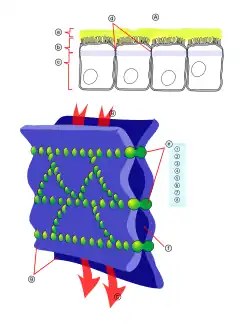

Die Tight Junctions

Die Endothelzellen sind über feste Zell-Zell-Verbindungen, die sogenannten Tight Junctions, miteinander verbunden. Diese Tight Junctions stellen dichte Verbindungen zwischen benachbarten Zellen dar und liefern einen wesentlichen Beitrag für die Schrankenfunktion der Blut-Hirn-Schranke.[24][25] Denn sie dichten den Raum zwischen den Zellen ab und schließen so einen parazellulären Transport, die Passage von Stoffen längs des interzellulären Spaltraums zwischen benachbarten Endothelzellen an diesen vorbei, praktisch aus.[26][27][28]

Mehrere Transmembranproteine, wie Occludin, verschiedene Claudine und Junctional Adhesion Molecules (JAM), verknüpfen die Endothelien im apikalen Bereich der lateralen Zellwände durch umlaufende Proteinbänder in Tight junctions, und unterbinden damit die parazelluläre Passage via Zwischenzellspalt zweier Endothelzellen für größere Moleküle weitgehend.[29] Die einzelnen Protein-Protein-Verbindungen wirken wie parallel verschaltete Sicherungen. Die Endothelzellen der Blut-Hirn-Schranke exprimieren von den 24 bekannten Claudinen nur Claudin-5 und Claudin-12. Claudin-5 wird dabei als wichtigstes Zelladhäsionsprotein der Blut-Hirn-Schranke angesehen.[30] Das Ausschalten (Gen-Knockout) des CLDN5-Gens, das für Claudin-5 codiert, führt bei Mäusen dazu, dass die Blut-Hirn-Schranke für Moleküle mit einer molaren Masse von bis zu 800 g·mol−1 durchlässig wird. Die so genetisch veränderten Tiere verstarben innerhalb weniger Stunden nach ihrer Geburt.[31]

Bei peripheren Kapillaren findet der Stofftransport zu Organen und Muskeln im Wesentlichen durch Fenestrierungen und Intrazellularspalten statt. Bei einem gesunden und intakten zerebralen Endothel sind die einzelnen Endothelzellen untereinander über die Tight Junctions dicht verbunden. Die Kapillargefäße des Gehirns lassen daher hauptsächlich nur einen transmembranen Stofftransport zu, der zudem von den Zellen besser als der parazelluläre Transport geregelt werden kann.[99] Wasser, Glycerin und Harnstoff sind Beispiele für kleine polare Verbindungen, die durch die Tight Junctions der Blut-Hirn-Schranke hindurchdiffundieren können.[100]